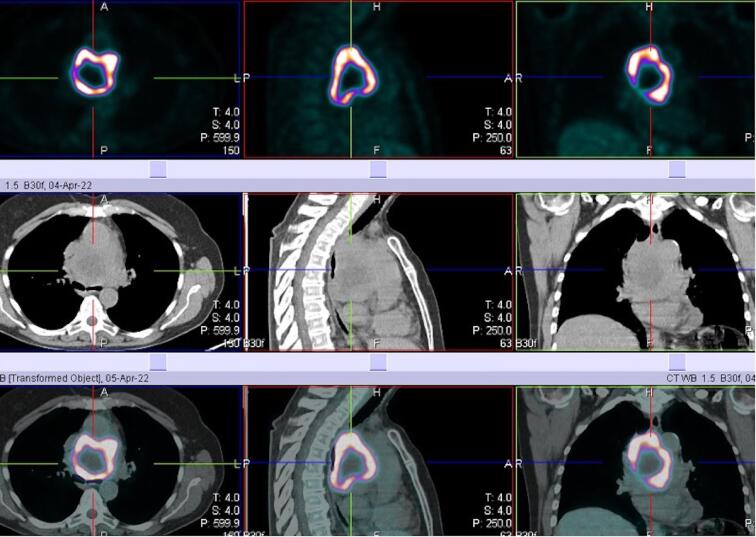

无功能性中纵隔副神经节瘤是一种罕见病。我们描述了一例 67 岁女性的病例,她在胸部 CT 和 18F 氟脱氧葡萄糖正电子发射断层扫描后,通过支气管内超声经支气管针吸术确诊为大纵隔副神经节瘤。肿瘤长约 9 厘米,位于上腔静脉和升主动脉后部之间,压迫左心房、气管和左主支气管,后方环绕右肺动脉。单孔右侧视频胸腔镜活检未得出结论,并发严重出血,但已得到控制。手术通过经胸腔经心包入路进行,然后进行心肺旁路和升主动脉切除,这样可以很好地暴露并更好地控制大血管和心脏。除左侧声带麻痹外,肿瘤完全切除,无围手术期并发症。12 个月后,患者已无疾病,全身状况良好。

A non-functional middle mediastinal paraganglioma is a rare entity. We describe a case of a 67-year-old woman with a diagnosis of a big mediastinal paraganglioma by endobronchial ultrasound transbronchial needle aspiration after chest CT and 18F-fluorodeoxyglucose positron-emission tomography. The nine centimeter in length tumor was located between the superior vena cava and the posterior portion of the ascending aorta, compressing the left atrium and the trachea and main left bronchus, posteriorly, surrounding the right pulmonary artery. Uniportal right video-thoracoscopic biopsy was unconclusive and complicated by severe hemorrhage, however controlled. Surgical resection was performed via a trans-sternal trans-pericardial approach followed by cardiopulmonary bypass and ascending aorta resection which allows an excellent exposure and greater control of great vessels and heart. Complete resection of the tumor was achieved without perioperative complication except for the left vocal cord palsy. Twelve months late the patient is disease free and in good general conditions.